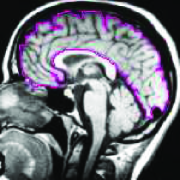

Appearance is one of the most important visual cues to distinguish between different structures in an image. Appearance is described by studying the distribution of different features such as intensity values in gray-scale images, color, and texture inside each object. In most cases, appearance models are incorporated into the data term in (2) and (7). The purpose of incorporating appearance prior is to fit the appearance distribution of the segmented objects to the distribution of objects of interest, e.g. using Gaussian mixture model (GMM) (Rother et al., 2004). In the literature, there are two ways to model the appearance: 1) adaptively learning the appearance during the segmentation procedure, and 2) knowing the appearance model prior to performing segmentation (e.g. by observing the appearance distribution of the training data). In the former case, the appearance model is learned as the segmentation is performed (Vese and Chan, 2002) (computed online). In the second case, it is assumed that the probability of each pixel belonging to particular label is known, i.e. if represents a particular set of feature values (e.g. intensity/color) associated with each image location for object, then it is assumed that is known (or pre-computed offline). This probability is usually learned and estimated from the distribution of features inside small samples of each object. Figure 9 illustrates the probability of different structures (the kidney, the tumour, and the background) in an endoscopic scene. A lower intensity in Figures 9(b-d) corresponds to higher probability.